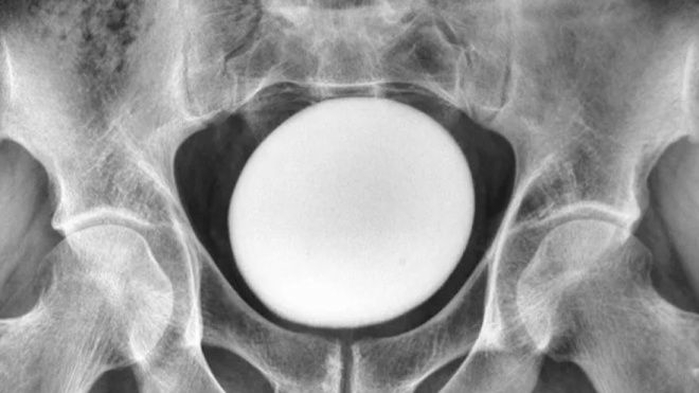

이란 35세 남성의 방광에서 발견된 타조알 크기의 결석 / 라이브사이언스 이란 35세 남성의 방광에서 발견된 타조알 크기의 결석 / 라이브사이언스

의료진이 환자의 복부를 촉진 검사한 결과, 치골 상부에서 거대하고 매끄러운 단단한 덩어리가 발견됐습니다. 이 물체는 골반이나 복벽에 유착되지 않은 상태였습니다.

초음파 검사를 통해 확인한 결과, 이 물체는 지름 약 11㎝에 달하는 달걀 형태로 나타났습니다. 의료진은 이를 비정상적인 크기의 방광 결석으로 진단했습니다.

수술을 통해 적출된 결석은 무게 826g, 길이 약 13㎝, 너비 10㎝, 높이 8㎝에 이르는 거대한 크기였습니다. 보고서는 이처럼 수술적 제거가 필요한 거대 결석 사례가 "매우 드물다"고 평가했습니다.